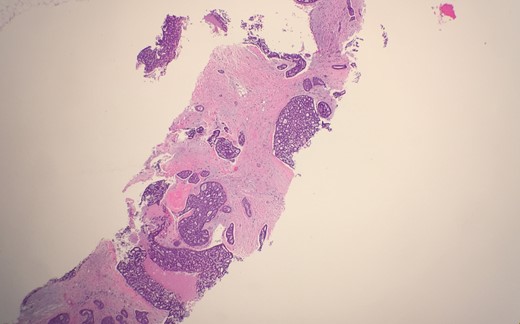

Microscopic examination from an ultrasound guided core-needle biopsy from the 7–8 o'clock retro-areolar region shows tumor composed of both luminal and basal cells (small bland myoepithelial cells with scant cytoplasm and dark compact angular nuclei surround pseudoglandular spaces with mucin) (Fig. 1). Immunohistochemical stain p63 positive for basal cells (Fig. 2). Combined with morphological features, this immunoprofile supports the diagnosis adenoid cystic carcinoma. The suspicious mass in the right breast 7–8 o'clock and the left breast 2 o'clock both showed stromal fibrosis and adenosis.

Microscopic examination from an ultrasound guided core-needle biopsy from the 7–8 o'clock retro-areolar region shows tumor composed of both luminal and basal cells (small bland myoepithelial cells with scant cytoplasm and dark compact angular nuclei surround pseudoglandular spaces with mucin).